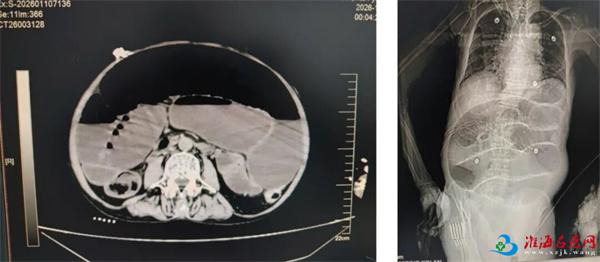

2026年1月10日凌晨,萧县黄口镇81岁的丁大爷(化名),因腹痛3天,在当地医院治疗效果不佳,呼叫120转入徐州一院,到急诊医学科时,患者出现意识模糊,血压骤降至60/30mmHg。腹部CT提示:腹盆腔肠管走行扭曲,多发肠管扩张、积气积液、部分可见气液平。初步诊断:肠梗阻、休克。

术前腹部CT

术前腹部CT非手术综合